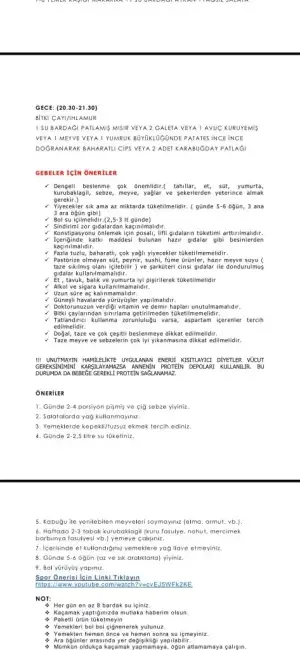

Folik asit içmelisin tabiki gebelikten önce bile içiyorlar. Folat değerin yetersiz değil ama nörolojik bir problem olmasın diye ilk 3 ay gebeler içer. Ama folik asiti doğal yoldan alma fikrini benimseyenler de var. Ben almanı öneritim doktoruna telefonda sorma ihtimalin var mı?Kızlar herkes folic asit içmeye başladı mı?

İlaç içmeme multivitamin vs takviyeye gerek var mı sizce?

Hamilelerde bu değerler kaç olmalı.